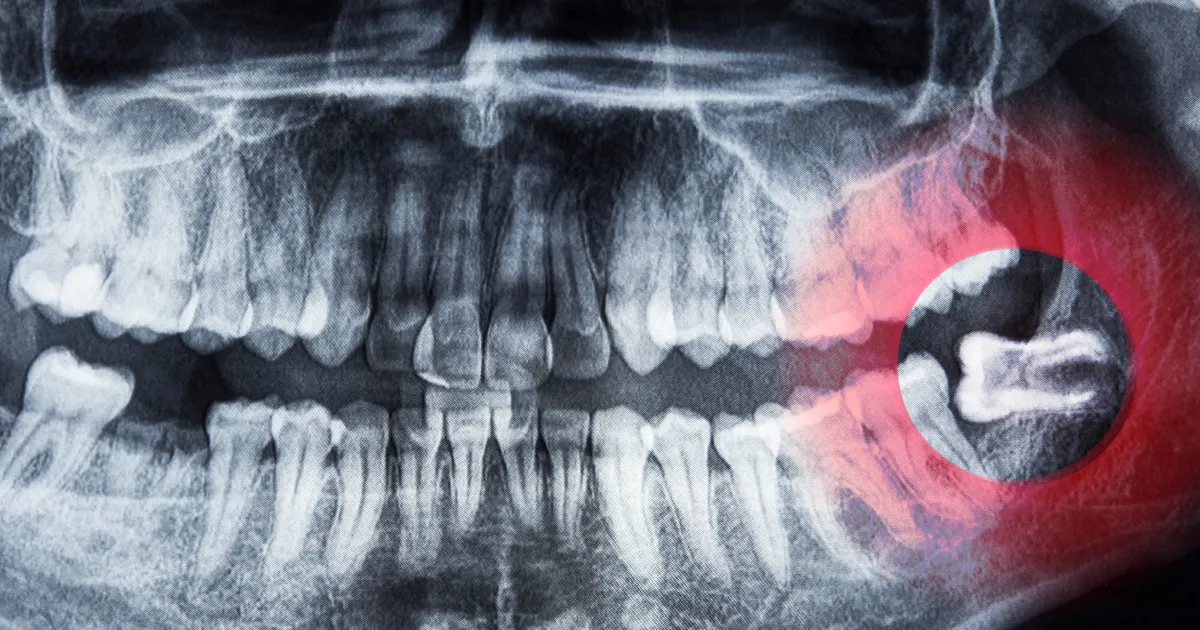

最新设备确保精确诊断

齿科ハミール高田88配备了先进的CT扫描和3D扫描仪器,如iTero,这些设备能够帮助医生对智齿的位置、形状以及周围的骨骼结构进行精确分析,确保手术的安全性和有效性。通过CT立体成像,医生能够清晰地掌握神经和血管的位置,从而在拔除过程中减少风险。